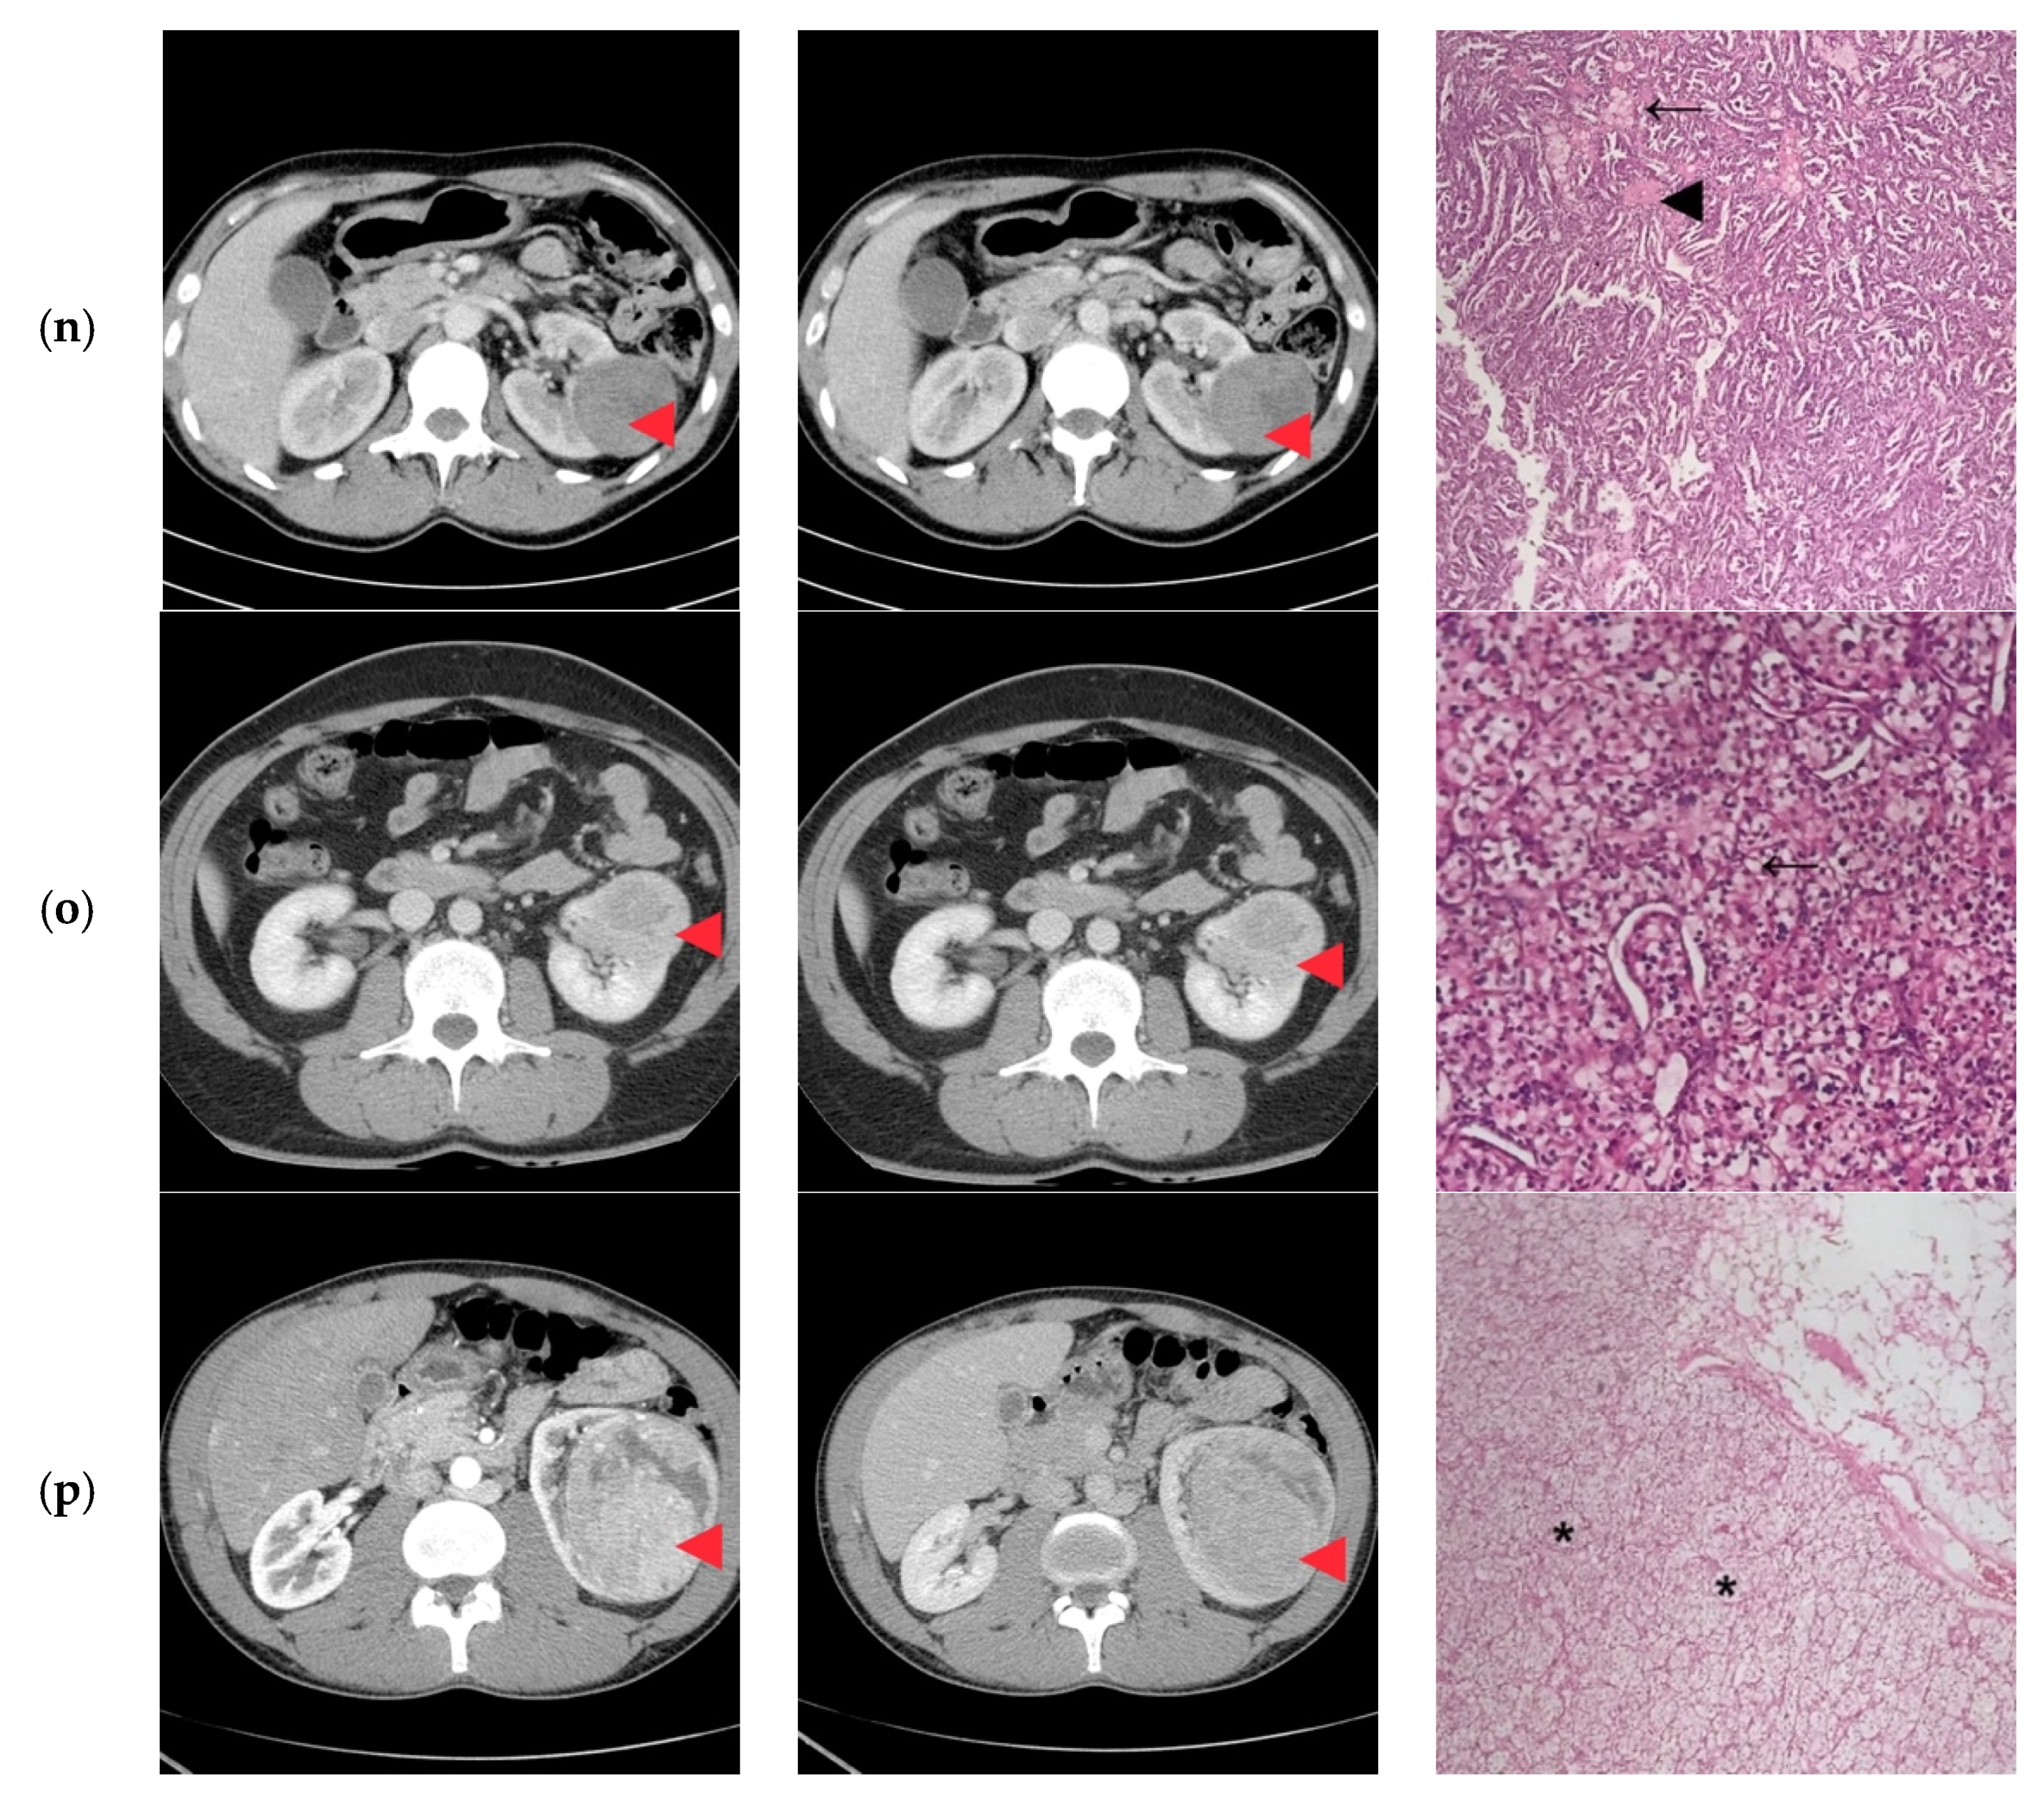

| 1 | 45/M | cT2N0 | 73 | 9 | Clear Cell RCC |

| 2 | 27/F | cT1bN0 | 60 | 8 | Clear Cell RCC |

| 3 | 38/M | cT1bN0 | 47 | 10 | Papillary/Clear Cell RCC Oncocytoma |

| 4 | 24/M | cT2N0 | 85 | 10 | Clear Cell RCC |

| 5 | 31/F | cT1aN0 | 35 | 8 | Papillary Clear Cell RCC |

| 6 | 41/M | cT2N0 | 86 | 10 | Clear Cell RCC |

| 7 | 29/M | cT1bN0 | 40 | 8 | Oncocytoma |

| 8 | 30/F | cT1bN0 | 44 | 10 | Papillary/Clear Cell RCC |

| 9 | 32/F | cT1bN0 | 52 | 11 | Clear Cell RCC |

| 10 | 25/M | cT1bN0 | 45 | 11 | Papillary/Clear Cell RCC Complicated cyst Oncocytoma/Fat poor AML |

| 11 | 43/F | cT1bN0 | 50 | 9 | Papillary RCC/Oncocytoma Fat poop AML |

| 12 | 41/F | cT2N0 | 73 | 10 | Oncocytoma |

| 13 | 43/M | cT3aN0 | 33 | 7 | Clear Cell RCC |

| 14 | 38/F | cT1bN0 | 50 | 8 | Bleeding Clear Cell RCC |

| 15 | 32/M | cT3aN0 | 55 | 10 | Clear Cell RCC |

| 16 | 37/M | cT2N0 | 93 | 11 | Clear Cell RCC |

| 1 | Retroperitoneoscopic radical nephrectomy | pT2N0 | Clear Cell RCC Furhman 2 | Yes |

| 2 | Open radical nephrectomy | pT1bN0 | Clear Cell RCC Furhman 1 | Yes |

| 3 | Retroperitoneoscopic radical nephrectomy | pT1bN0 | Papillary-RCC, type II | Yes/No |

| 4 | Open Radical nephrectomy | pT2N0 | Cystic Nephroma | No |

| 5 | Retroperitoneoscopic radical nephrectomy | pT1aN0 | Clear Cell RCC Furhman 1 | Yes/No |

| 6 | Open radical nephrectomy | pT2N0 | Clear Cell RCCFurhman 2 | Yes |

| 7 | Open partial nephrectomy with local renal hypothermia and hilar clamping | PT1bN0 | Multicentric Chromophobe-RCC | No |

| 8 | Open partial nephrectomy with local renal hypothermia and hilar clamping | pT1bN0 | Clear Cell RCC Furhman 1 | Yes/No |

| 9 | Retroperitoneoscopic radical nephrectomy | pT1bN0 | Clear Cell RCC Furhman 2 | Yes |

| 10 | Open partial nephrectomy with local renal hypothermia and hilar clamping | pT1bN0 | Multiloculated cystic Clear Cell RCC Furhman 1 | No |

| 11 | Open partial nephrectomy with local renal hypothermia and hilar clamping | pT1bN0 | Metanephric adenofibroma | No |

| 12 | Open radical nephrectomy | pT2N0 | Oncocytoma | Yes |

| 13 | Open partial nephrectomy–segmentary renal vein invasion–radical nephrectomy | pT3aN0 | Clear Cell RCC Furhman 1 | Yes |

| 14 | Open partial nephrectomy with local renal hypothermia and hilar clamping | pT1bN0 | Papillary-RCC, type I | No |

| 15 | Open radical nephrectomy | pT3aN0 | Clear Cell RCC Furhman 1 | Yes |

| 16 | Retroperitoneoscopic radical nephrectomy | pT2N0 | Clear Cell RCC Furhman 1 | Yes |